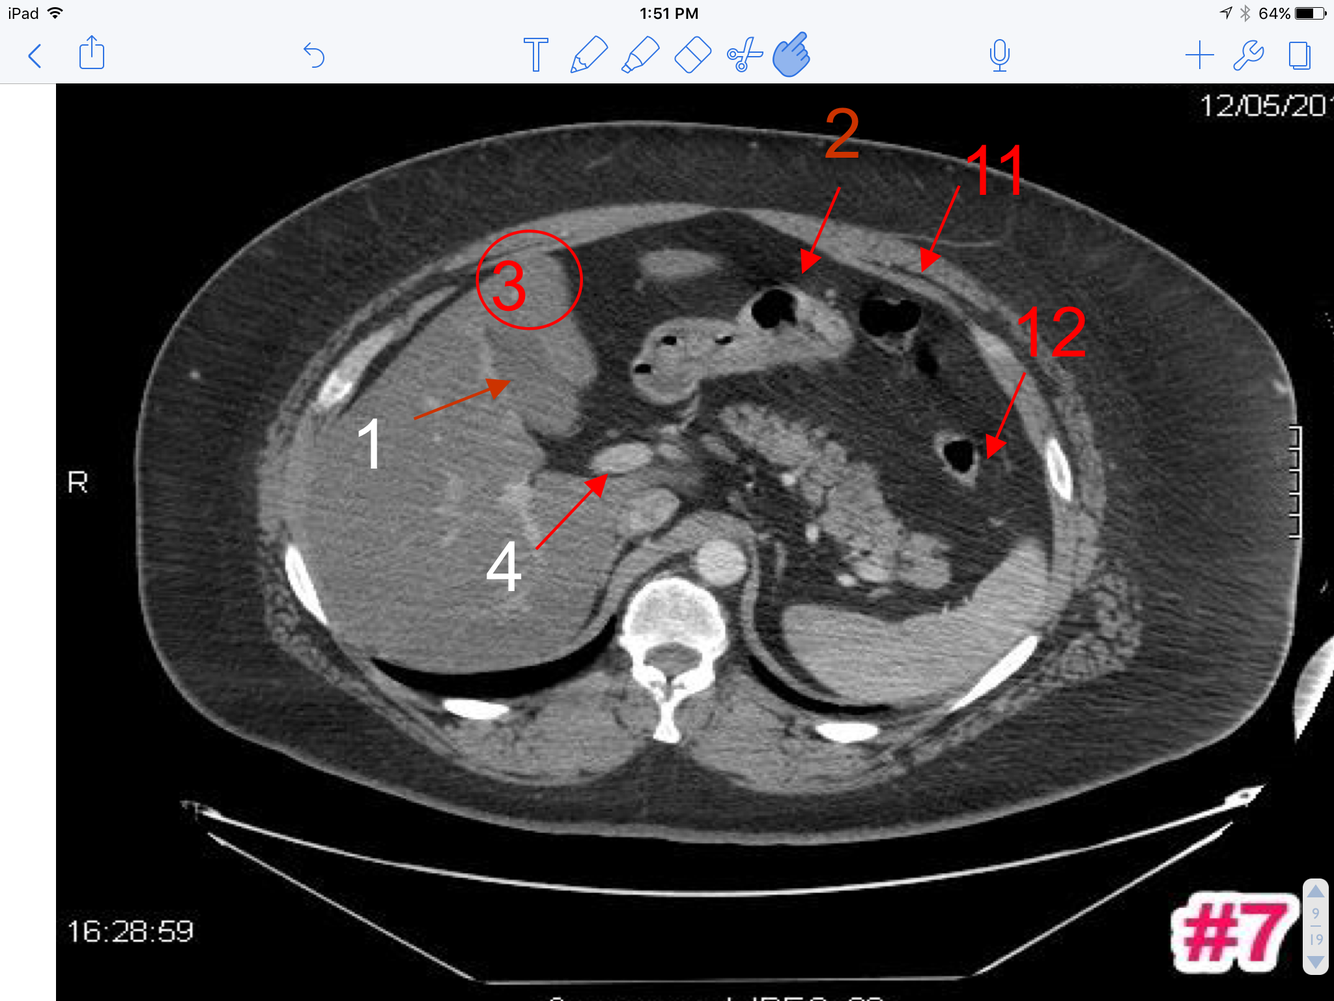

7

A

1. Body of gallbladder

2. Pyloric part of the stomach

3. Quadrate lobe of liver

4. Portal vein

5. Transverse colon

6. Descending colon